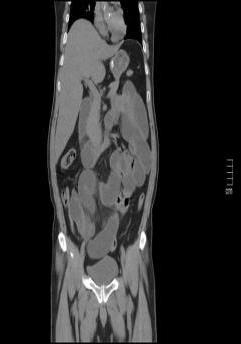

• 单侧双通道内镜下椎间盘切除术治疗钙化型腰椎间盘突出症的临床疗效分析

2025, 31(8):26-31. DOI: 10.12235/E20240693

摘要 (204) HTML (119) PDF 3.09 M (137) 评论 (0) 收藏

摘要:目的 观察单侧双通道内镜(UBE)下椎间盘切除术治疗钙化型腰椎间盘突出症(CLDH)的临床疗效。方法 回顾性分析2020年1月-2022年1月在该院行UBE下腰椎间盘切除术的25例单节段CLDH患者的临床资料。记录手术时间、术后住院时间和术后并发症情况。采用腰腿痛视觉模拟评分法(VAS)评分、腰椎日本骨科协会(JOA)评分和Oswestry功能障碍指数(ODI),评估术前、术后3 d、术后1个月和末次随访的临床疗效。末次随访时,采用改良Macnab标准,评估优良率。结果 术后随访12~24个月,平均(15.60±2.60)个月。手术时间为(58.67±10.73)min,术后住院时间为(4.65±0.63)d。术后3 d、术后1个月和末次随访时的VAS评分和ODI明显低于术前,JOA评分明显高于术前,差异均有统计学意义(P < 0.05)。末次随访时,根据改良的Macnab标准,15例为优,9例为良,1例为可,优良率为96.00%(24/25)。术后并发症:1例神经根腹侧硬膜囊撕裂,长度约5 mm,未行硬膜囊修补术,术后嘱患者卧床5 d,给予补液治疗,患者下床活动未诉头痛等不适,术后MRI显示:未见硬膜外大量积液;1例出现下肢感觉障碍,给予营养神经药物对症治疗,术后1个月随访时恢复。术后影像学检查显示:游离钙化组织基本被完全切除,神经根得到充分减压。末次随访时,未发现复发病例。结论 UBE下腰椎间盘切除术治疗CLDH安全、有效,值得应用于临床。